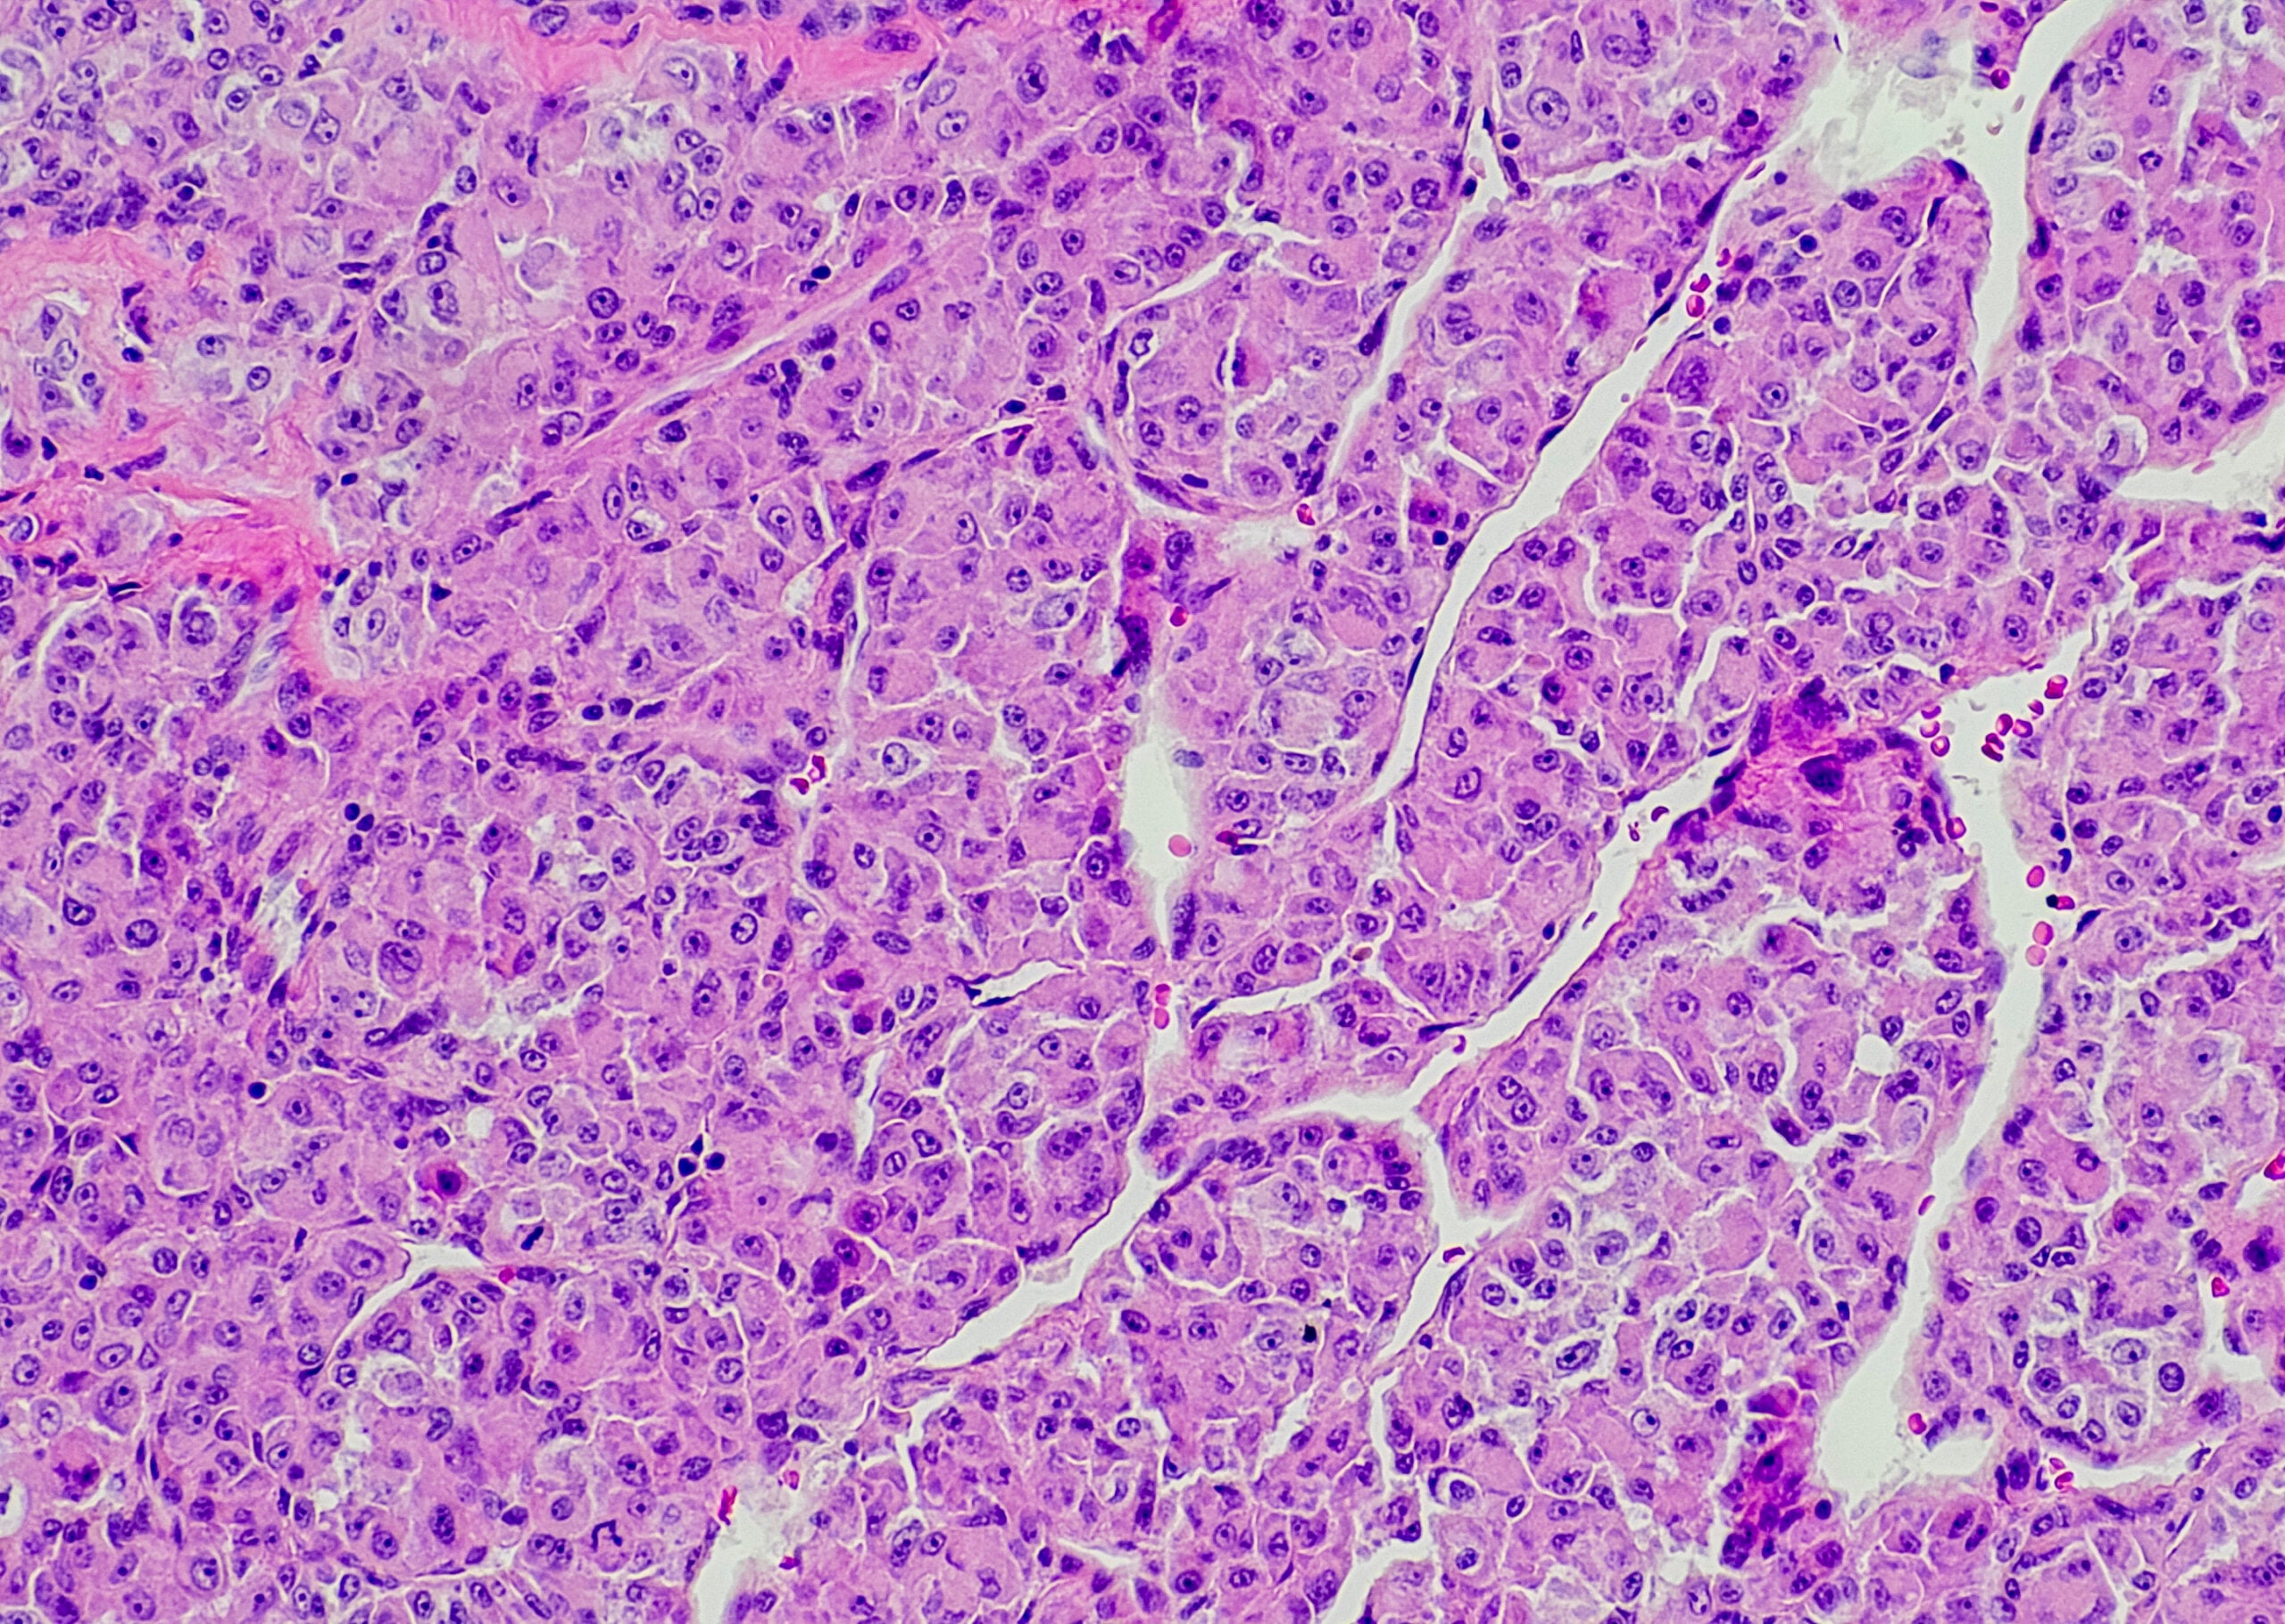

Multilocular cystic renal cell carcinoma (MCRCC)